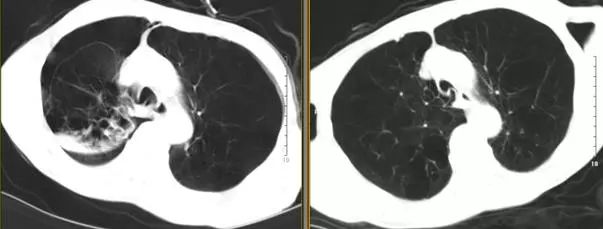

高分辨胸部CT提示:肺气肿以双肺上叶为著,右肺上叶肺大疱,中叶呈外压性条索状,右侧斜裂完整。

图7 术前2天(右)与术后5天(左)胸部CT对比